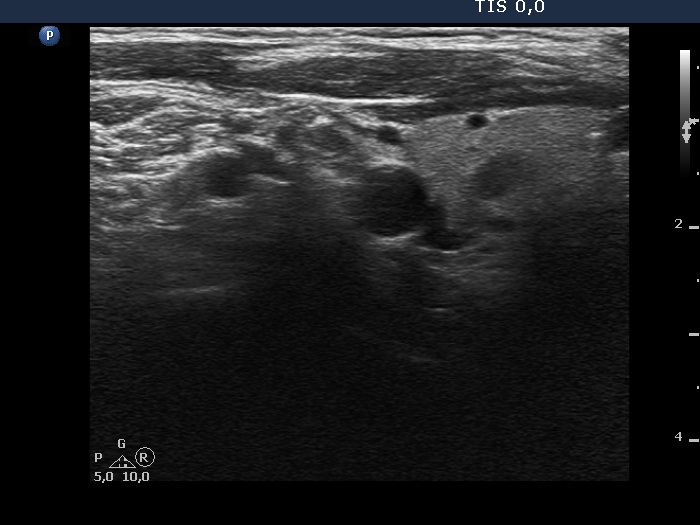

The borders of the nodule - case 2050 (ultrasonographic picture 7)

Right lobe, longitudinal scan

Lateral to the right lobe, longitudinal scan. This hypoechoic mass could be either a lymph node or a muscle fiber.